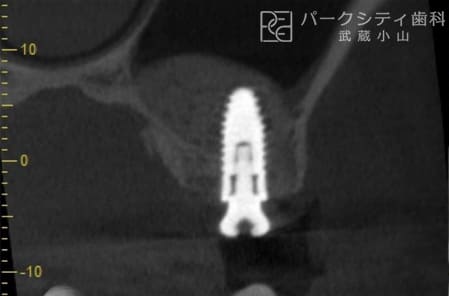

CASE.02

上顎洞挙上術にて骨の高さを確保し、インプラント治療した症例

顎骨が足りなく他医院でインプラント治療を断られた方のケースです。上顎洞挙上術を用いて顎骨を確保し、インプラント治療をおこないました。